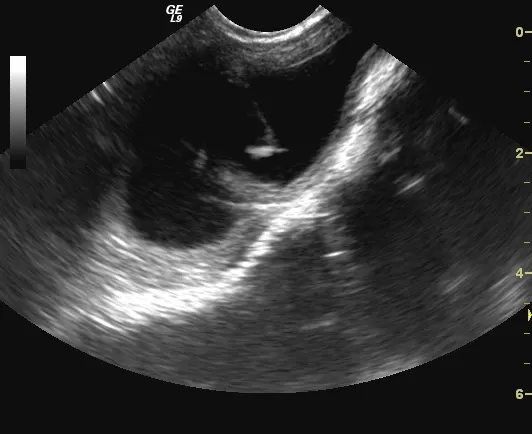

Ultrasound-guided cystocentesis could also be used to safely obtain a urine sample. This method can be done freehand or with a biopsy guide and is done without biopsy gel-sterile saline or alcohol is applied over the biopsy site. Insert the needle close to the transducer, keeping the needle within the plane of the ultrasound beam. After verification that the tip of the needle has advanced to the desired position in the bladder lumen, aspirate urine into the syringe (Figures 5A and 5B).